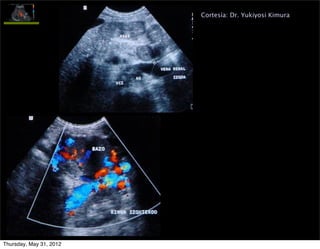

Permeabilidad vena paraumbilical

• Colateral portosistémica (caput medusae)

• Porta izquierda  v.paraumbilical  v.pared abdominal

Importancia de su dx: 1. podría prevenir la aparición

de VE, PERO 2. riesgo EH

Cortesía: Dr. Yukiyosi Kimura